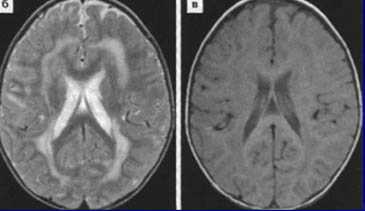

Туберозный склероз. Гамартомы. КТ, Т2-зависимая МРТ и FLAIR

Корковые узлы - самое частое проявление туберозного склероза. Они расположены в коре головного мозга, деформируют её, захватывают прилегающее белое вещество и подвергаются кальцификации . При МРТ узлы изоинтенсивны серому веществу на Т1-взвешенных МРТ и чуть гиперинтенсивнее его на Т2-взвешенных. Контрастирование наблюдается в 5% случаев. В белом веществе обнаруживаются тяжи , отходящие радиально от желудочков. Корковые узлы и тяжи нередко называют «гамартомами», хотя они представляют собой скорее демиелинизацию и кальцификацию, чем истинную гетеротопию.

Субэпендимальные, то есть проецирующиеся в желудочек, но растущие со стороны паренхимы мозга, узлы чаще расположены рядом с хвостатым ядром или гипоталамической бороздой сразу за отверстием Монро, реже в области III, IV желудочков и Сильвиева водопровода. На Т2-взвешенных томограммах субэпендимальные узлы умеренно гиперинтенсивны и часто содержат кальцинаты . От астроцитом их отличает не столь яркий сигнал и меньшие размеры. Контрастирование при введении препаратов гадолиния иногда наблюдается и в субэпендимальных узлах , и всегда в астроцитомах.

Туберозный склероз. Субэпендимальные узлы. Аксиальная Т-зависимая МРТ.